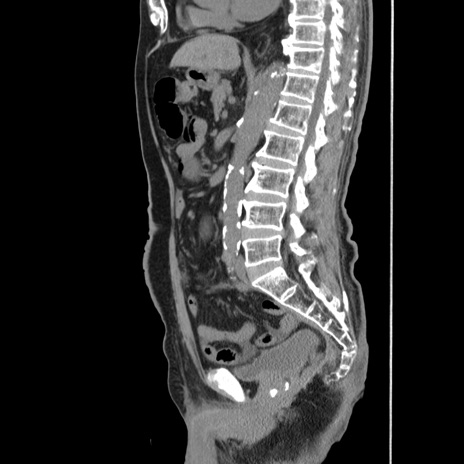

症例24(矢状断像)

【症例】80歳代男性

【主訴】左側腹部痛、嘔吐

【現病歴】本日早朝より左腹部に痛みあり。昼頃嘔吐認めたため、救急要請。

【既往歴】直腸癌(Mile手術)、胆摘

【身体所見】意識清明、BT 35.9℃、BP 221/93mmHg、SpO2 97%(RA) 、腹部:左ストーマ周囲に限局性の腹部膨隆あり。 膨隆部自発痛・圧痛あり・軟。